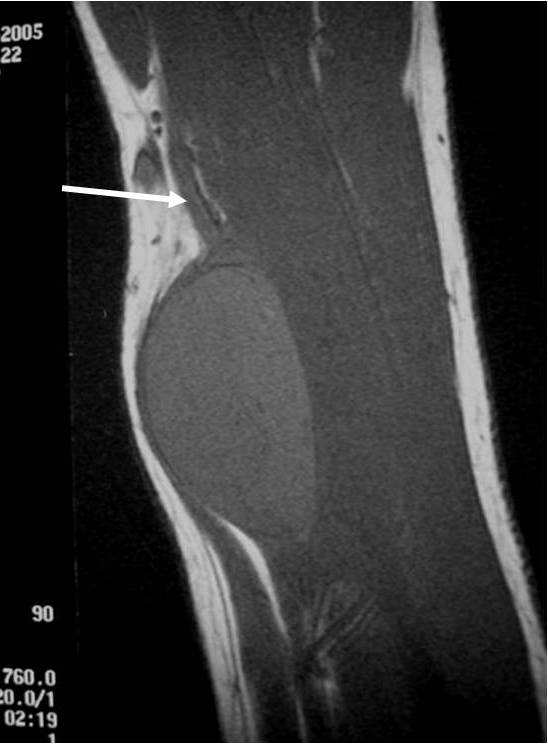

MRI appearance (Fig. 1 – 4)

• Nerve: Tubular structure visualized entering and exiting the mass (may be difficult to see with small lesions or lesions of the trunk or retroperitoneum) (Fig. 2 & 4)

Fig. 1-4 MR image demonstrates a 5 cm intermuscular mass in the anterior compartment of the arm arising along the course of the neurovascular structures. Isointense to muscle on T1W image and heterogeneous high signal on T2W with low signal in the central area (Antoni A) and peripheral high signal (Antoni B), known as “Target Sign”. Coronal image shows a structure entering and exiting the mass (median nerve).